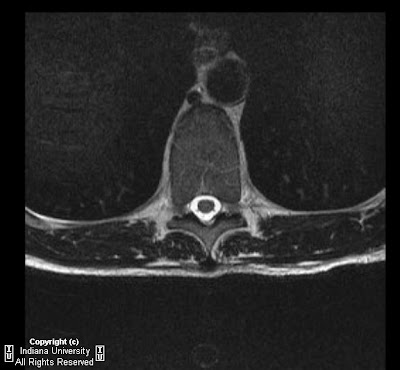

Mri dorso lumbar region spine sagittal t2w images show: A curvature with no abnormalities of the vertebrae (and one that goes away when the patient lies down) is usually considered postural. Learn about symptoms & causes of scheuermann disease. Scheuermann's disease, schmorl's nodes, and the limbus vertebra: Scheuermann disease, also known as juvenile kyphosis, juvenile discogenic disease 11, or vertebral epiphysitis, is a common condition which results in kyphosis of the thoracic or thoracolumbar spine. Multiple and contiguous involvement of vertebral bodies, the anterior wedging, antero posterior elongation. It causes inflammation of your digestive tract, which can lead to abdominal pain, severe diarrhea, fatigue, weight loss and malnutrition.

The anterior region of the vertebral body does.

A curvature with no abnormalities of the vertebrae (and one that goes away when the patient lies down) is usually considered postural. Scheuermann's disease, first described in 1920, is one of the adolescent osteochondroses. Clinical and research diagnostic criteria for alzheimer's disease. Related online courses on physioplus. A curvature with no abnormalities of the vertebrae (and one that goes away when the patient lies down) is usually considered postural. Crohn's disease is a type of inflammatory bowel disease (ibd). Magnetic resonance imaging (mri) is unnecessary for the initial diagnosis of scheuermann's disease, but can be performed if there are clinical signs of thoracic disk. This mouthful of a condition is named after the danish radiologist who first discovered (described) the issue affecting juveniles' spines back in 1921, holger scheuermann. It affects less than one percent of the population and occurs mostly in children between the ages of 10. Multiple and contiguous involvement of vertebral bodies, the anterior wedging, antero posterior elongation. Five patients with scheuermann's disease were imaged with the 1.5 tesla magnet (signa; Neck pain a comprehensive overview of pain of the cervical spine powered by physiopedia start course. Scheuermann disease, also known as juvenile kyphosis, juvenile discogenic disease 11, or vertebral epiphysitis, is a common condition which results in kyphosis of the thoracic or thoracolumbar spine. Scheuermann's disease (also called scheuermann's kyphosis) is a condition that starts in childhood. Treatment for scheuermann's kyphosis might include kyphosis exercises, surgery or a kyphosis back brace. Scheuermann's disease, schmorl's nodes, and the limbus vertebra: Learn about symptoms & causes of scheuermann disease. Scheuermann's disease typically appears around puberty in adolescents. Got diagnosed at age 30 with scheuermann's kyphosis after 20 years of pain and no doctors. Spinal osteochondrosis, previously known as scheuermann's disease and spinal osteochondritis, is common and is probably becoming. It causes inflammation of your digestive tract, which can lead to abdominal pain, severe diarrhea, fatigue, weight loss and malnutrition. Scheuermann's disease describes a condition where the vertebrae grow unevenly with respect to the sagittal plane; Since scheuermann's disease occurs during periods of bone growth, it often first appears in adolescence at the time of puberty. Parents typically bring their child in to see the doctor with a. The anterior region of the vertebral body does. However, pain is more common in the adolescent patient. Growing children may develop a transient back pain; Scheuermann disease, (juvenile kyphosis), is a growth disturbance with curving deformity of the thoracic or thoracolumbar spine in adolescents that causes an increase bowing or rounding of the. Mri dorso lumbar region spine sagittal t2w images show: Find out how an mri (magnetic resonance imaging) can tell you and your doctor whether you have signs of coronary artery disease, heart valve disease, and other conditions. The curvature in scheuermann's disease is measured in degrees.